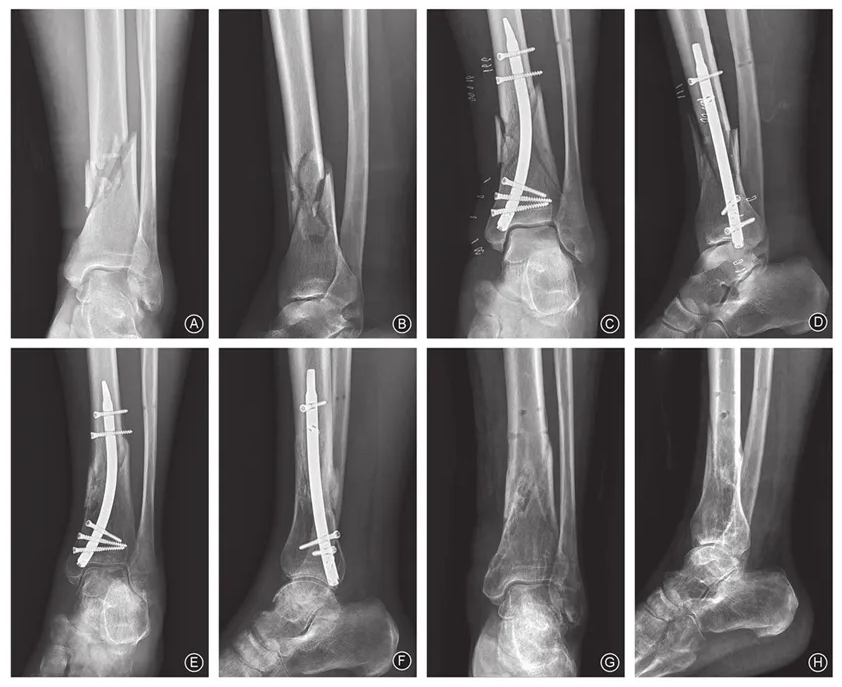

Under epidural or general anesthesia, the patient is placed supine. A pneumatic tourniquet (60 kPa) is applied to the proximal thigh. After standard disinfection and draping, closed reduction is attempted with fluoroscopy; reduction clamps or minimally invasive tools may be used. The entry point at the medial malleolus is confirmed fluoroscopically: on the AP view, it is 4 mm (for φ7 nail) or 5 mm (for φ8 nail) above the medial cortex; on the lateral view, it aligns with the central axis of the medial malleolus.

A 2 cm longitudinal incision is made on the medial malleolus, between its anterior and posterior margins. The superficial deltoid ligament is exposed and split longitudinally. A proximal protection sleeve is placed, and a guide pin is inserted parallel to the medial cortex until it reaches the outer cortex of the metaphysis. Fluoroscopy confirms proper position.

A hollow reamer is advanced along the guide pin to the stop mark, followed by a solid reamer. A trial nail determines the optimal length: short nails for metaphyseal fractures, long nails if the fracture extends into the shaft. The targeting jig is connected via locking bolts. The nail is inserted; resistance may require gentle rotation.

Under jig guidance, three distal cancellous screws and two proximal cortical screws are placed. If fibular fracture is present, it must be reduced and fixed first to restore length and alignment and avoid tibial malalignment. Postoperatively, ankle rotation tests assess stability. Final fluoroscopy confirms reduction and fixation.

Entry point: AP view – 4 mm (φ7) or 5 mm (φ8) above medial cortex; lateral view – central axis of medial malleolus.

Incision: 2 cm medial longitudinal cut, deltoid ligament split, sleeve placement.

Reduction and nailing:

• Fix fibula first if fractured.

• Insert guide pin parallel to medial cortex.

• Ream and insert nail; lock with 5 screws (3 distal cancellous, 2 proximal cortical).